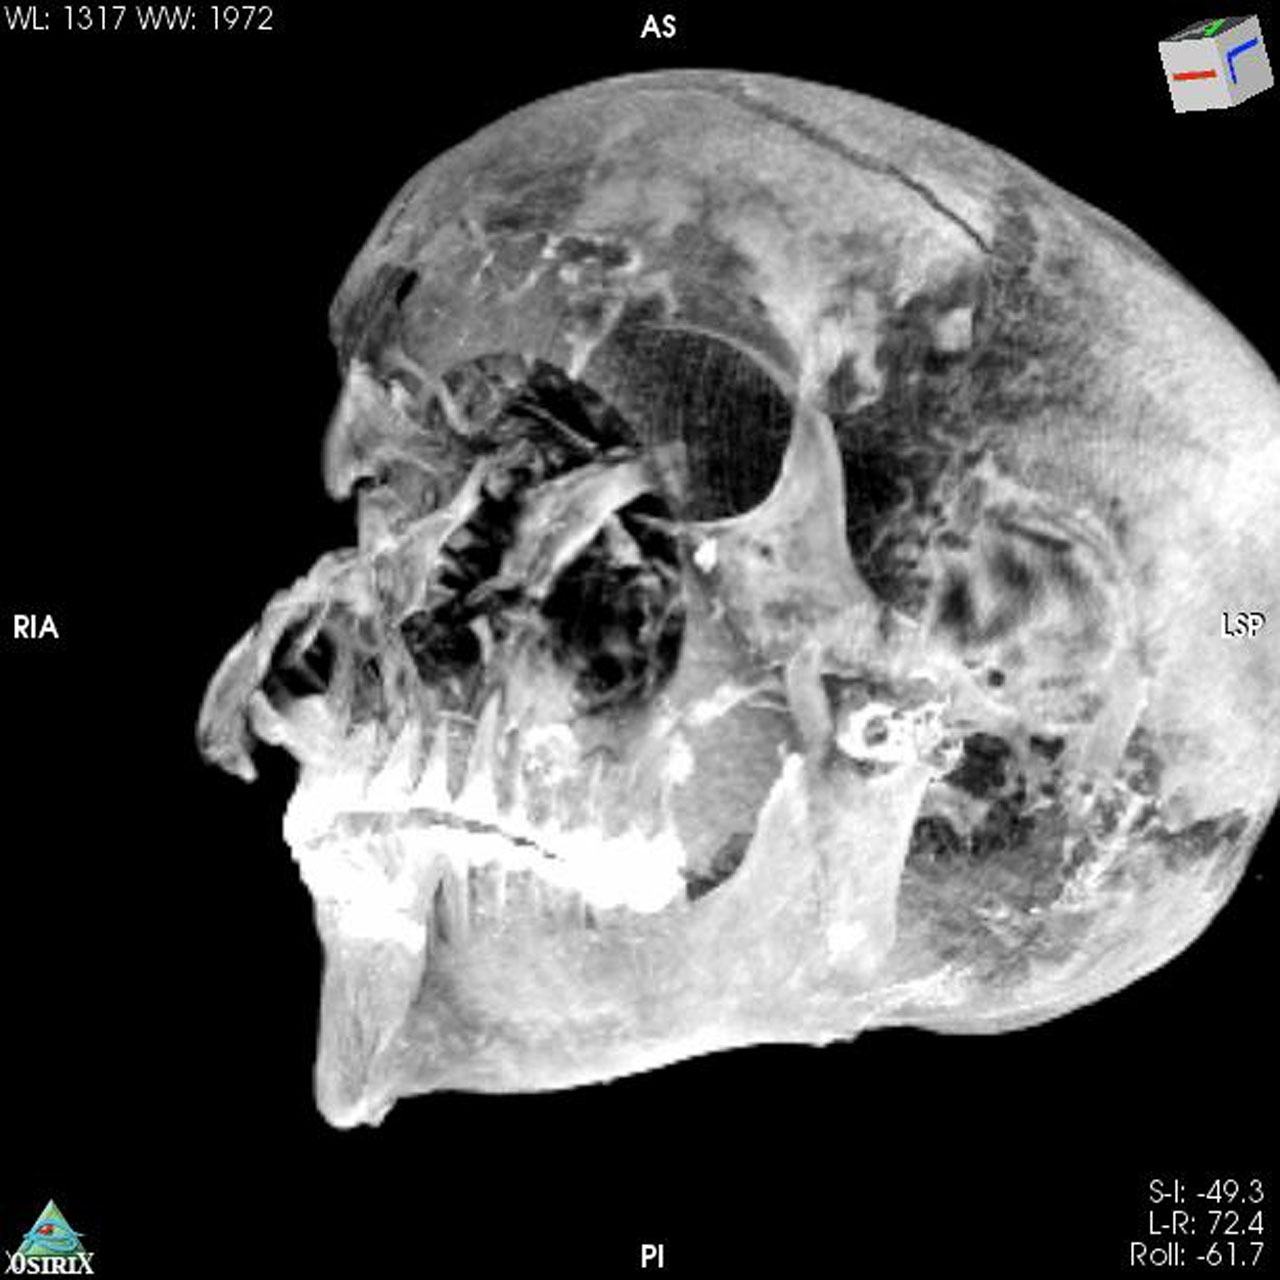

The CT scans discovered something interesting in the form of previously undetected lesions that embalmers concealed. The new paper has found that the pharaoh was likely captured on the battlefield, and his hands were tied behind his back to prevent him from defending against the attack. The team believes that the death of Seqenenre-Taa-II was a ceremonial execution.

The ancient pharaoh was about 40 years old when he died, based on morphology revealed in the new CT images. CT images also revealed that the embalmers used a sophisticated method to hide the head wounds under layers of embalming material that functioned like fillers used in plastic surgery. The researchers believe the mummification took place in a real mummification laboratory rather than being performed hastily as previous studies suggested.